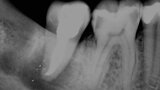

Fig. 3: Pre-op periapical radiograph.